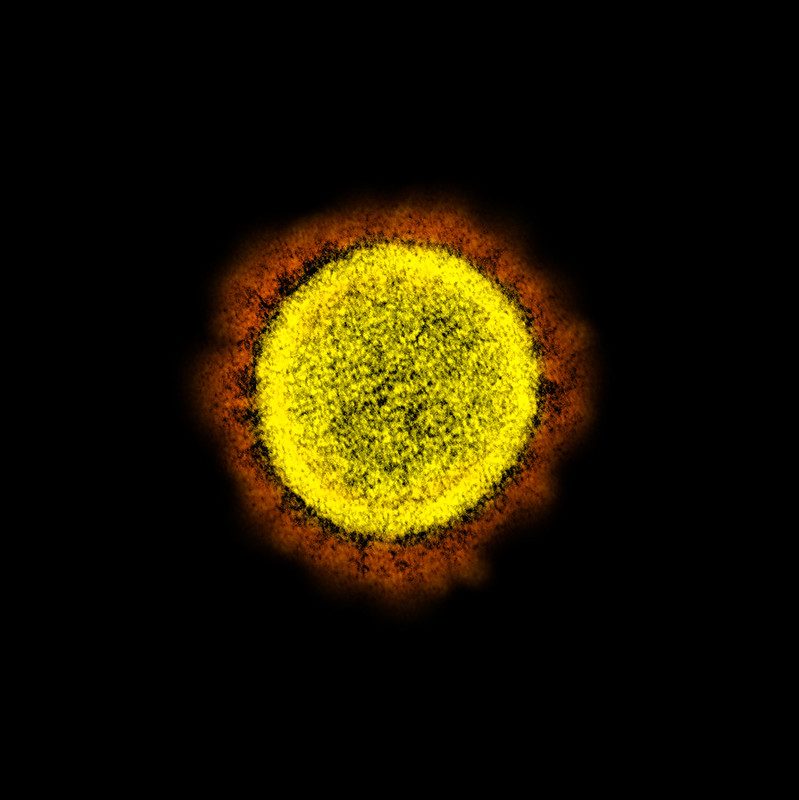

Resulta que los investigadores de este centro sacaron fotografías microscópicas del coronavirus atacando células humanas, mostrando detalles nunca antes vistos.

Las distintas imágenes del COVID-19 se obtuvieron con un microscopio de electrones y después fueron coloreadas artificialmente para mostrar diferentes detalles del patógeno.

El coronavirus mide entre 120-160 nanómetros de diámetro. Esto significa que son demasiado pequeños para ser vistos con un microscopio óptico y solo observables con un microscopio electrónico.